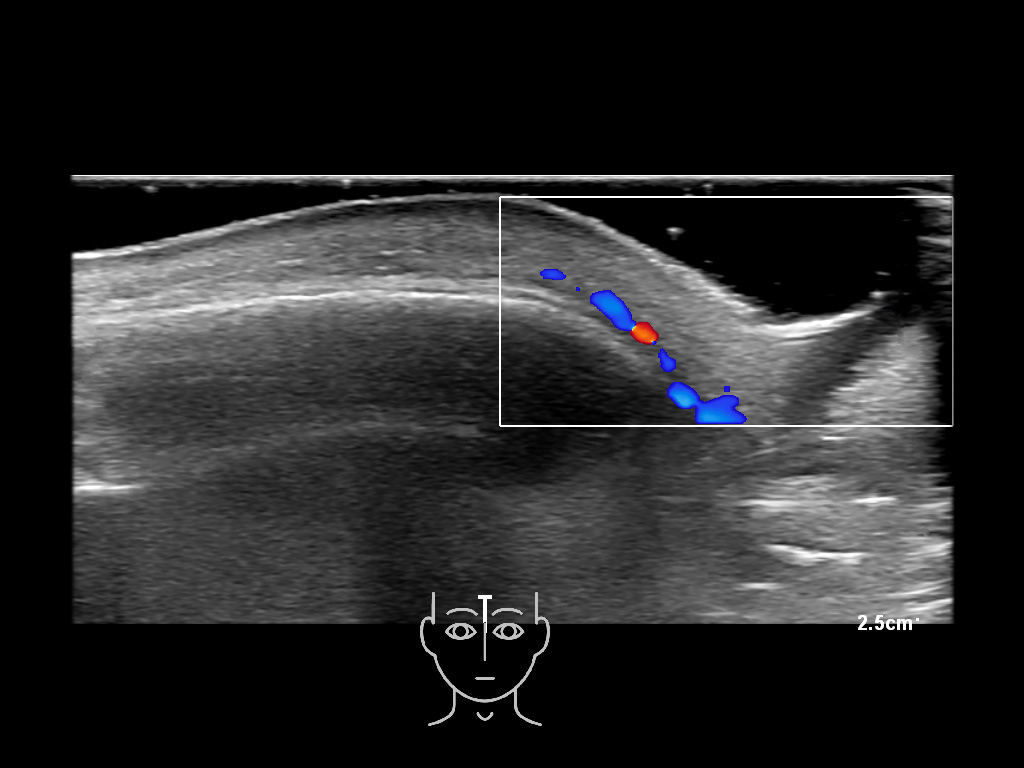

In this section you will learn more about the different layers of the face with the use of ultrasound. When you click on the secondary ultrasound image, you will see the different structures as an overlay. This will help to train yourself to recognize the different layers of the face.

Study the first image to recognize the different layers. If you are sure about the layers, swipe to the second image to view the answer (if applicable).